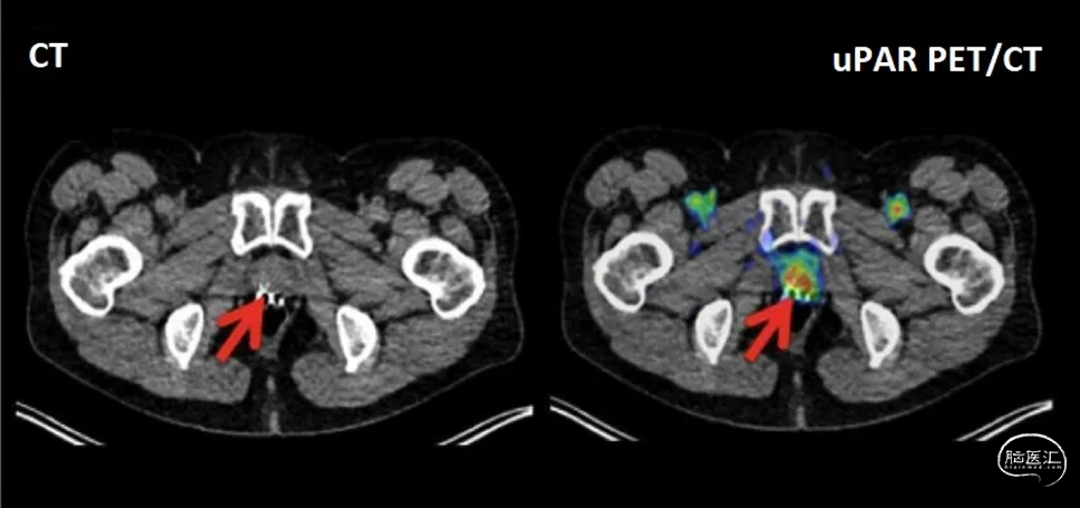

uTREAT®疗法基于Curasight旗下uTRACE®诊断技术的同一靶向配体开发,二者共同搭载于uPAR诊疗一体化平台。uTRACE®是基于uPAR-PET的影像诊断技术,2023年公布的uPAR-PET/MR II期研究结果已证实其对GBM具有高度的预后价值,可实现肿瘤的精准检测、风险分层,为治疗方案制定和疗效监测提供依据。目前,该技术已完成9项临床试验,涉及450名患者,涵盖8种实体瘤类型,并已建立商业化供应体系。

● 首例治疗患者的正电子发射断层显像(PET)显示,uTREAT®在肿瘤部位呈现清晰且持续的摄取,证实药物可成功靶向癌组织

● 药物显像信号在给药后至少24小时内仍清晰可辨,提示其与肿瘤的结合作用持久,具备向肿瘤有效递送辐射剂量的潜力

● 直至末次扫描(给药后24小时),患者体内PET信号仍持续存在,表明uTREAT®具备延长型结合动力学特征,可实现肿瘤吸收剂量最大化